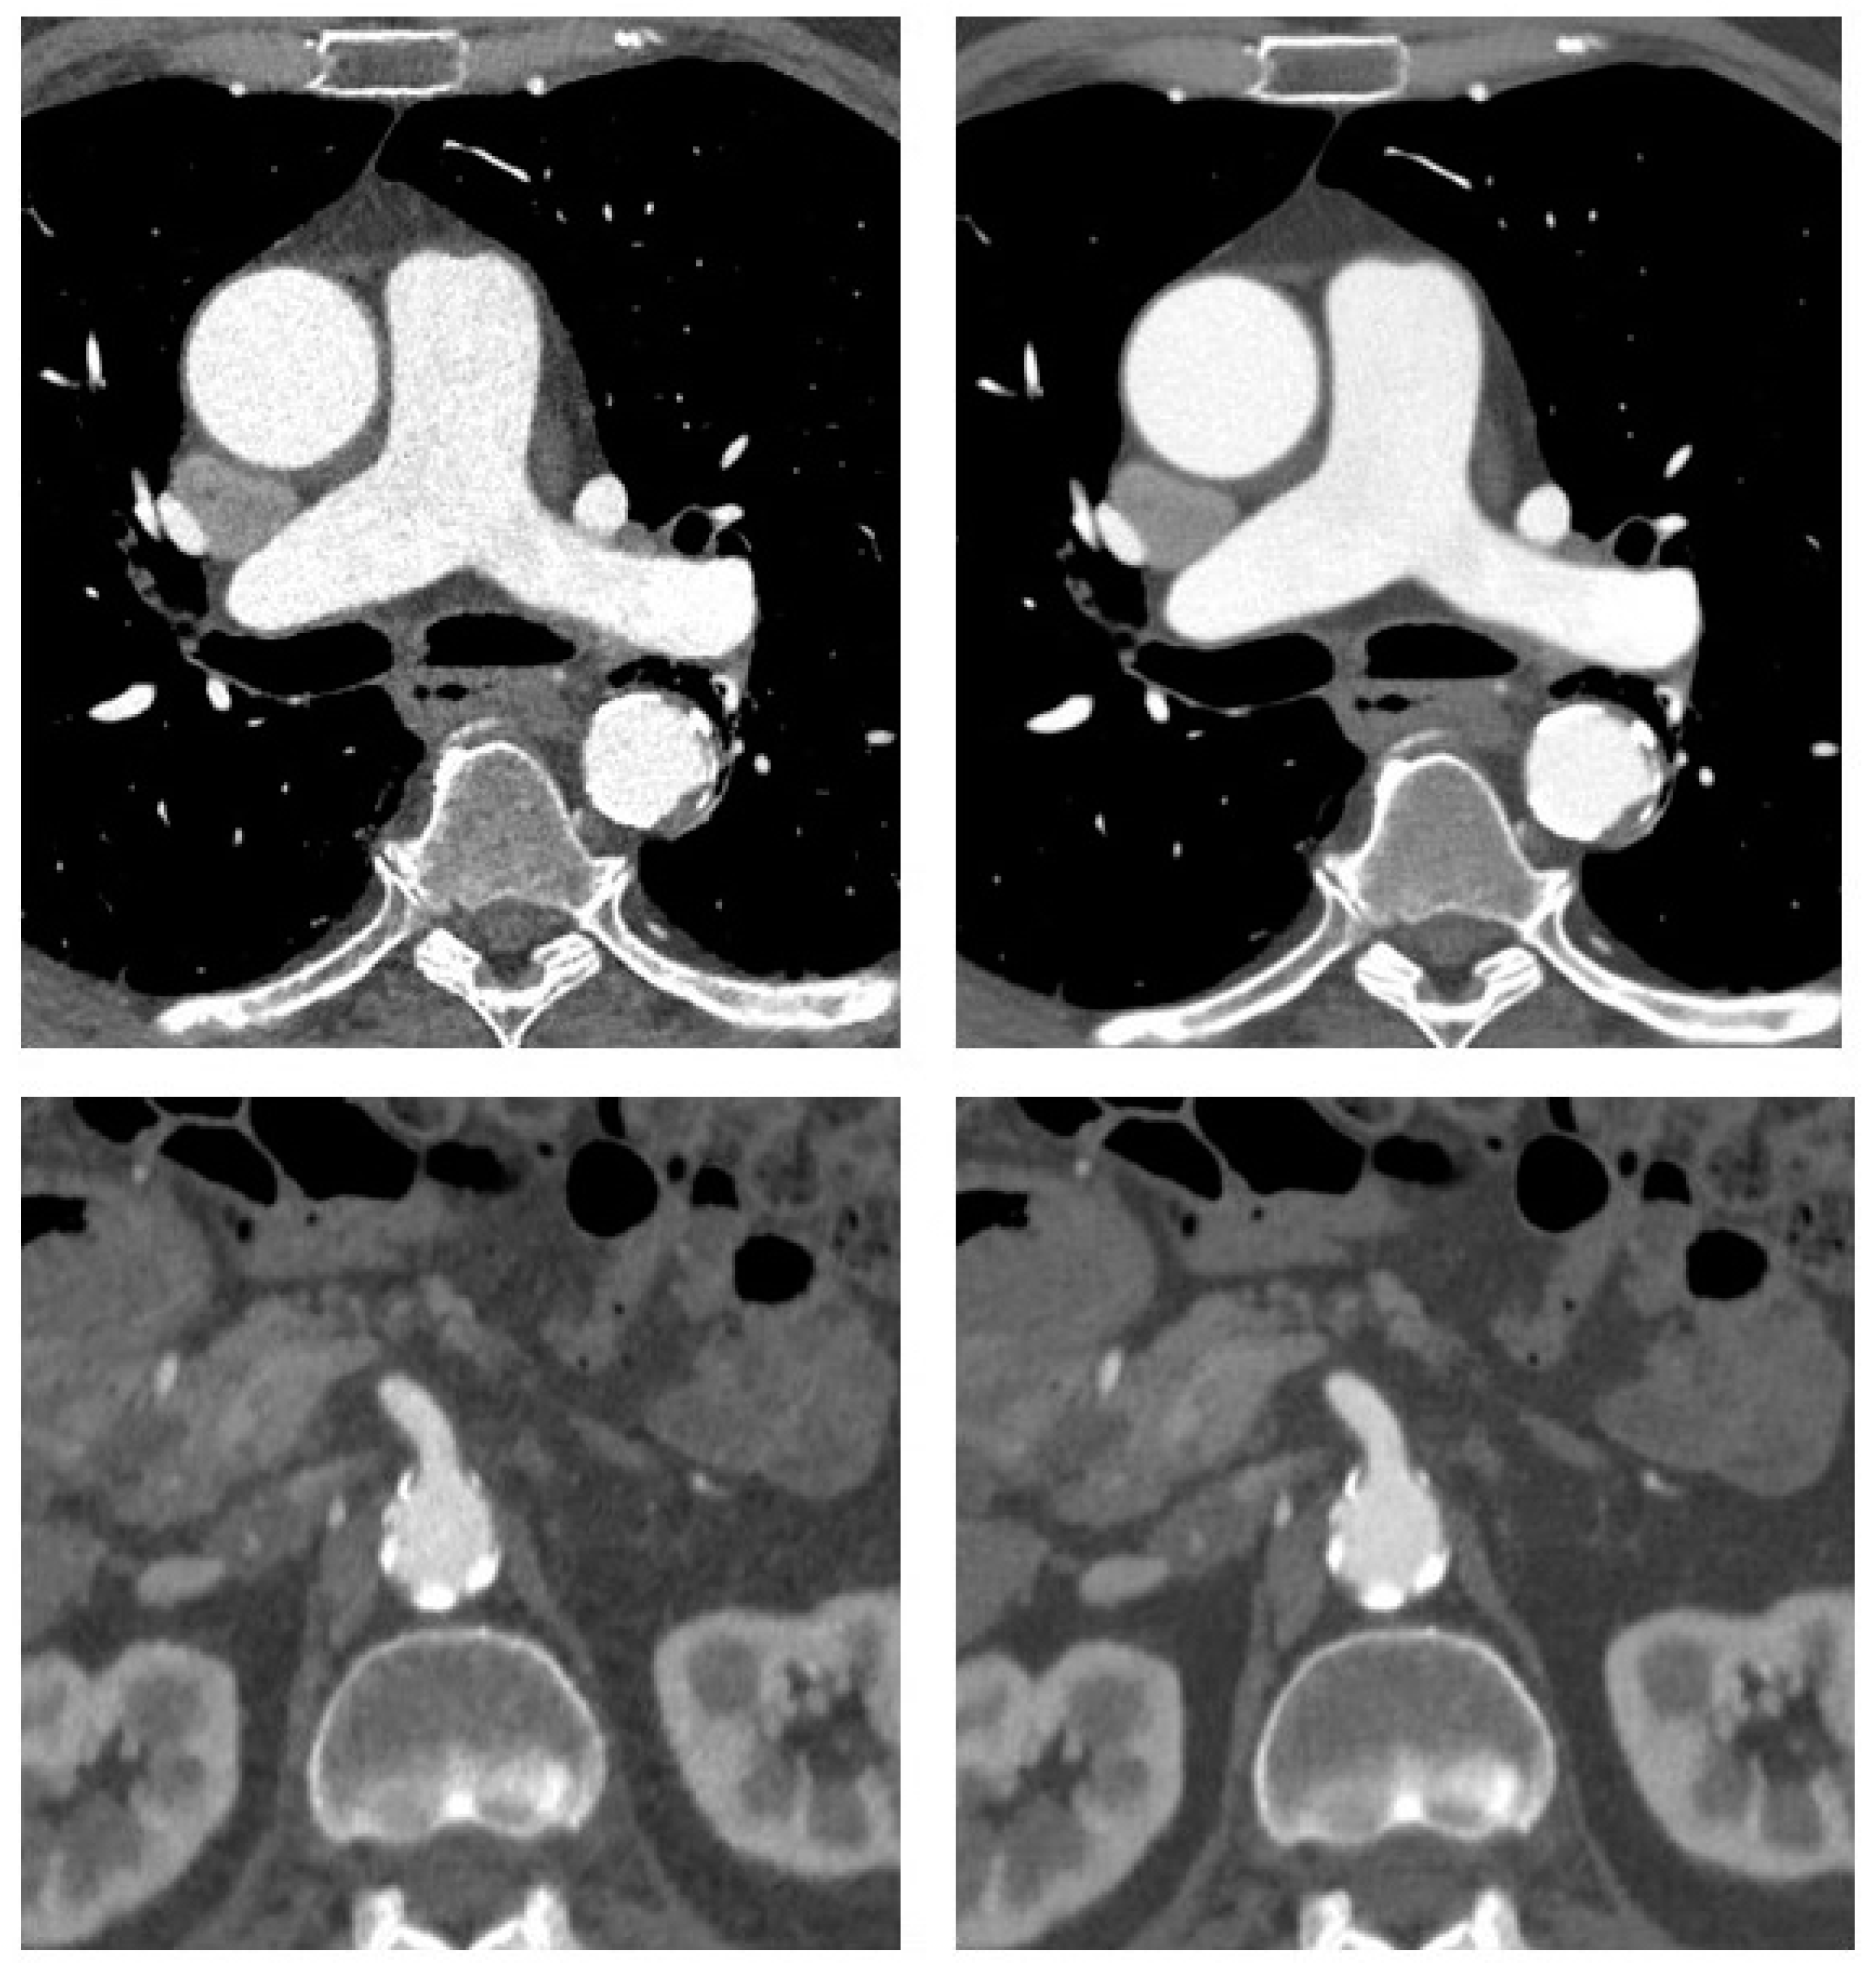

The median attenuation values in the paraspinal muscle and vascular lumen were without relevant differences between ASIR-V and DLIR (see Figure 3). Compared to ASIR-V, DLIR reduced median image noise by slightly more than 50% for the ascending aorta (22 vs. 48 Hounsfield units (HU)) and the descending thoracic aorta (23 vs. 47 HU, both p < 0.0001). Correspondingly, median SNR roughly doubled for the ascending aorta (18 vs. 9) and the descending thoracic aorta (17 vs. 8, both p < 0.0001). The same effect size was seen for CNR in the ascending aorta (15 vs. 7) and the descending thoracic aorta (14 vs. 7, both p < 0.0001). There was a roughly 40% reduction in image noise for the abdominal aorta (18 vs. 29 HU) and the iliac arteries (13 vs. 21 HU, both p < 0.0001), with an equivalent improvement in SNR (21 vs. 13 for the abdominal aorta, 27 vs. 17 for the iliac arteries, both p < 0.0001) and CNR (18 vs. 11 for the abdominal aorta, 23 vs. 14 for the iliac arteries, both p < 0.0001).

Figure 3.

Objective image quality. Figure 3 data are shown as boxplots with the whiskers ranging from the lowest to the highest value, with the box extending from the 25th to the 75th percentile and the median plotted as the line inside the box. Turquoise: ASIR-V = adaptive statistical iterative reconstruction V, magenta red: DLIR = deep learning-based image reconstruction, HU = Hounsfield units. For comparisons between DLIR and ASIR-V, the level of statistical significance is shown as n.s. for not significant, * for p < 0.01 and *** for p < 0.0001.

In obese patients (n = 17, median BMI 32.7 kg/m2), improvements in CNR ranged from 52% for the iliac arteries to 103% for the ascending aorta. In normal-weight patients (n = 17, median BMI 21.9 kg/m2), improvements in CNR were even more marked, ranging from 63% for the iliac arteries to 123% for the ascending aorta (Table 3).